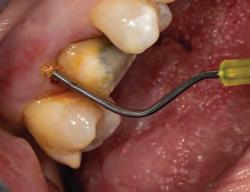

1. For restorations, Astingedent™ X hemostatic and Ultrapak cord are ideal for controlling blood and sulcular fluids and can also protect tissue from burs. Use a firm air/water spray to remove excess hemostatic solution.

1. Packing Ultrapak cord quickly displaces tissues and improves access for indirect veneer luting.